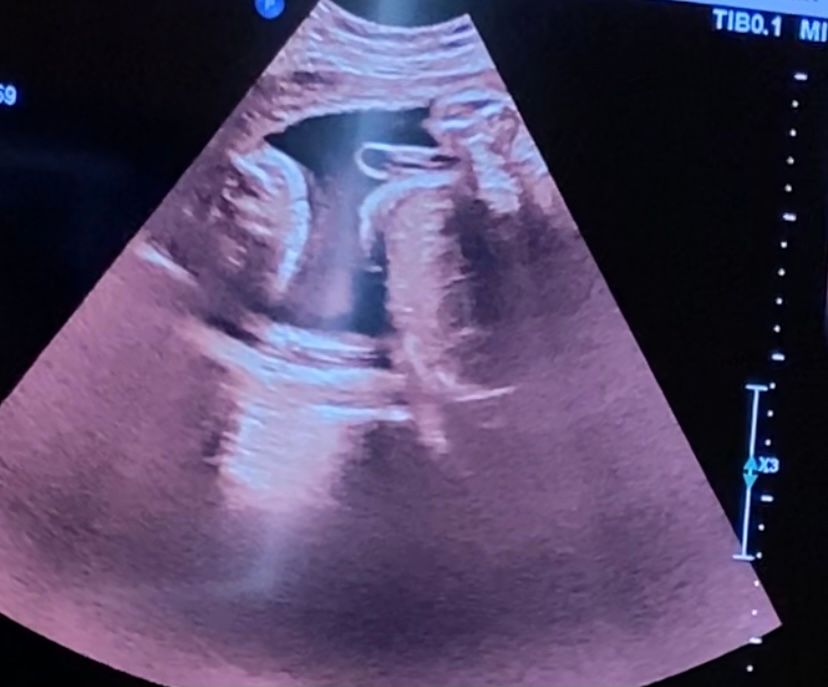

а вот пол , у моего врача с самого начала под вопросом, вроде и девочка ,но она почему то не уверена. Постоянно сжатые ноги. Мне конечно уже все равно, я уже и хочу девочку и готово все для неё ,но вот эта неуверенность немного мучает. Вот только такие фото,но ничего здесь не видно, да?

Это скорее всего пуповина,у вас малыш отчётливо показывает вам средний палец слева😂

Мол ,извините,не покажусь)

Фото конечно не очень... Руки бы вырвать узисту. По этому фото мальчика не видно, Но если ноги реально сжаты, то возможен и сюрприз.

А это не пипирка у нас?